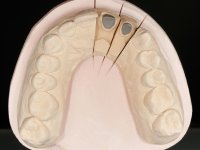

Foi feito o tratamento endodôntico dos dentes 2.1 e 2.2.de imediato, a sintomatologia que o paciente manifestava a isso impunha. Na mesma consulta foi realizada uma extensa gengivetomia com o bisturi elétrico, no sentido de expor os limites cervicais da fratura. Foram colocadas resinas compostas nos remanescentes radiculares com a intenção de reformular a emergência dos tecidos moles. Realizei a impressão dos remanescentes radiculares para confeção em laboratório de uma ponte provisória. A ponte provisória de 2 elementos, apresentava um formato que visava no futuro acomodar o coto dos espigões falsos cotos que iria ser cimentados nos remanescentes radiculares. Apresentava um reforço metálico palatino e dois apoios para os dentes adjacentes, um mesial e outro distal. Os remanescentes radiculares foram preparados para a confeção de dois espigões falso coto fundidos. As linhas de acabamento cervical foram definidas e os canais radiculares desobturados e preparados. A impressão foi realizada com a utilização de tutores de plástico com a técnica de dupla mistura. O afastamento gengival foi feito utilizando pasta de caolino. A ponte provisória foi rebasada em boca com acrílico auto polimerizavel, cimentada provisoriamente sobre as raízes e os apoios colados aos dentes adjacentes. No laboratório foram confecionados os E.F.C. fundidos, tendo o cuidado de preservar espaço para a definição no re preparo dentário da linha de acabamento cervical. Removida a ponte provisória foi feita a cimentação dos E.F.C. fundidos com cimento de ionómero de vidro reforçado com resina. A ponte provisória teve que ser retocada para permitir a acomodação dos cotos e simultaneamente foi readaptada à redefinida linha de acabamento cervical. Durante 2 meses a ponte provisória acompanhou a estabilização periodontal das raízes traumatizadas e simultaneamente conseguiu a maturação da arquitetura gengival.

Durante esse período foi também removida a férula dos dentes 1.3, 1.2 e 1.1 no sentido de avaliar a sua estabilidade. Esta remoção foi feita com muito cuidado para não danificar a superfície vestibular dos dentes. Foram utilizados discos de polimento de forma sequencial e taças de borracha. Após a repetição de testes de vitalidade verificou-se a necrose do dente 1.1, tendo sido realizado o necessário tratamento endodôntico. A impressão definitiva foi feita com a técnica de dupla mistura e o caolino utilizado como afastamento gengival. A ponte provisória foi mais uma vez rebasada. No laboratório, utilizando a tecnologia CAD-CAM, foi feita uma infraestrutura em Zr e posteriormente revestida com cerâmica. Durante este processo sentimos a necessidade de acrescentar resina composta por mesial do dente 2.3 com o objetivo de manter os diâmetros mesio-distais simétricos aos dentes do 1.1 e 1.2. Nesse sentido foi confecionada uma chave de silicone transparente que seria utilizada em boca para orientar esse acrescento. Na porção mesial da superfície palatina do dente 2.1 da ponte foi feita uma pequena cavidade que seria utilizada para colocar uma pequena férula de arame com o objetivo de assegurar a eventual abertura de um diastema. Em boca foi realizado um isolamento relativo e feito o acrescento de resina composta no 2.3 com a ajuda da chave de silicone. A ponte foi cimentada definitivamente com cimento de ionómero de vidro reforçado com resina. Finalmente foi colado uma pequena porção de arame entre a ponte e o dente 1.1.